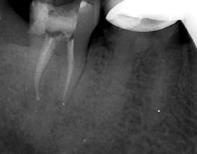

检查:全口卫生差,牙石++,软垢+,牙龈正常,有退缩。47牙远中合面龋坏,冷+,探-,叩+,松-.48牙近中阻生。 X线:47牙合面可见低密度暗影,累及髓腔,未行根管治疗。48牙近中阻生。

诊断:47牙急性牙髓炎;48牙阻生齿。 治疗计划:拔除阻生齿,并行47牙根管治疗。 治疗:拔除阻生齿后,阿替卡因局部浸润麻醉,47牙去净龋坏,开髓揭髓室顶,探查根管4根,牙髓摘除术,K锉初步预备,根管测长仪测量根管长度,各根管内导入根管润滑剂EDTA,protaper镍钛器械预备根管,冲洗,超声荡洗,水溶性氢氧化钙充填根管,暂封,约复诊。 复诊:一周后,诊间无不适,47

牙暂封完好,冷-,探-,叩-,不松。 试主尖,大锥度牙胶尖+AH-PLUS糊剂充填根管,热压充填牙胶,暂封。